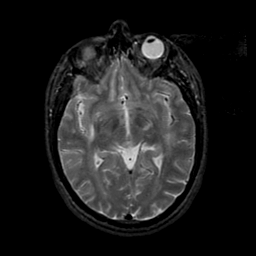

MR Study #21, November 3, 1991 -- Slice #23